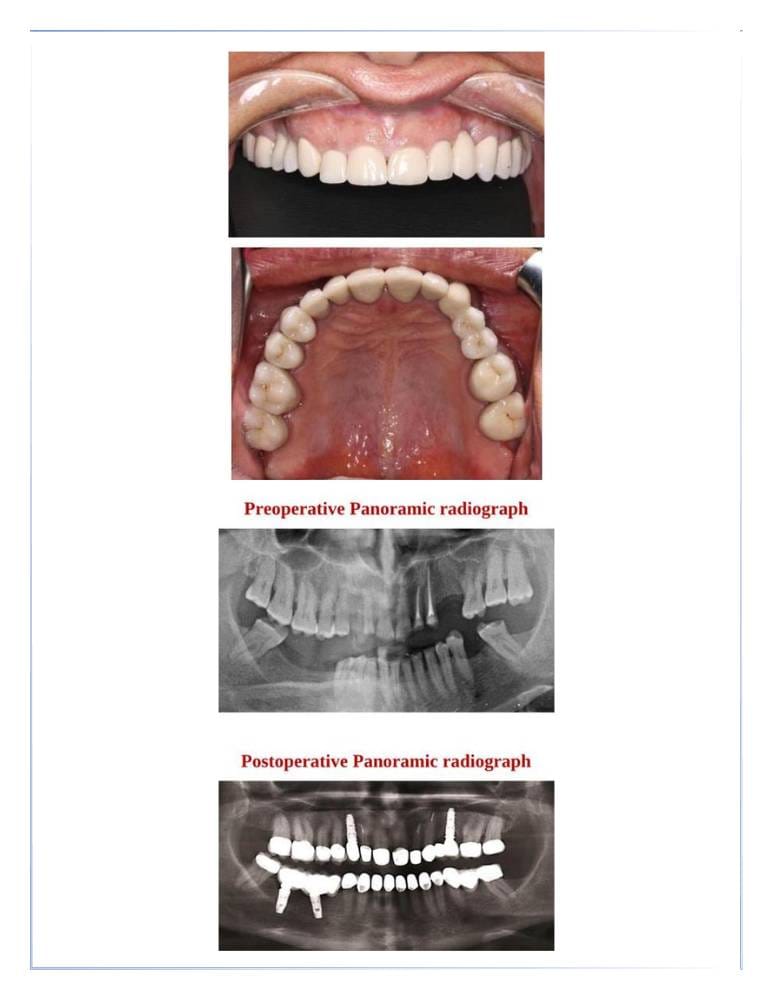

تركيبات الأسنان

- التيجان والجسور الثابتة.

- التركيبات التجميلية لتعويض الأسنان المفقودة.

زراعة الأسنان

- استبدال الأسنان المفقودة بزراعات دائمة.

- توفير الدعم للتركيبات المتحركة أو الثابتة.